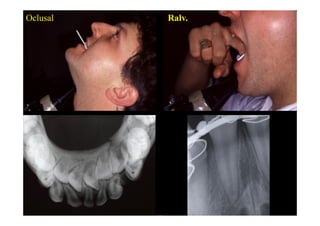

Oclusal                         Ralv.

• III. Imagerie

: mandibule

orthopantomographie

Dautrey, Bonneau

mordu, rétro